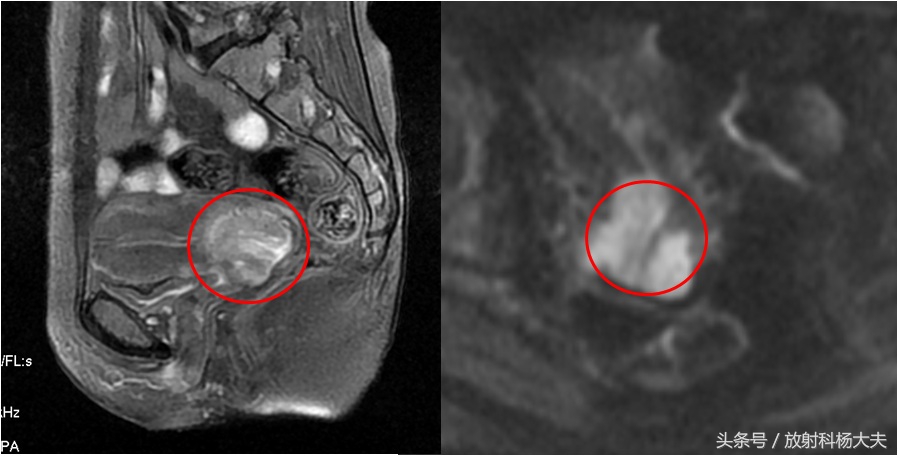

发现宫颈癌后,通常需要做MRI,目的是为了看病变侵犯的范围,也就是分期(早中晚期等),然后根据这个决定是手术,还是放疗等,但不幸的是,很多人发现的时候已经没有手术机会(参考本头条文章)。

红圈所示为宫颈的癌灶